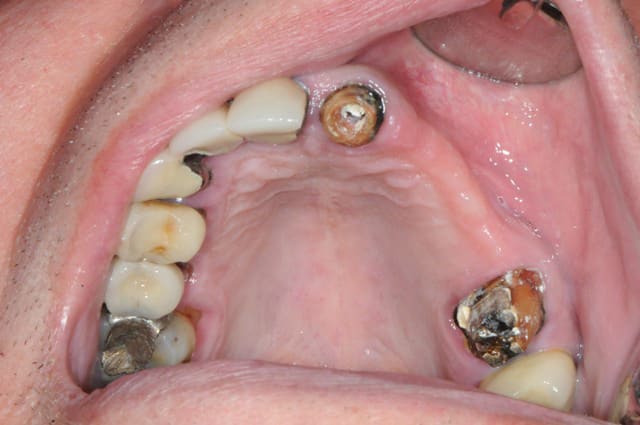

Patiente adressée suite à une ré-hab prothétique fait en 2010, perte de la canine 6 mois après...donc stellite plutôt mobile, comme la 14 et bientôt la 37, mais bon, on commence le projet implanto.

Exo de la 23 + implantation immédiate

Expansion kit Meissegner et lame 15

Pose de 2 implants (13 et 11)

Pose 22 impossible, j'ai tenté, mais crak, bof, j'ai placé en 24 et 25.

Un peu de granules osseuse (23)

Les photos sont de ma nouvelle 2e assistant implanto.